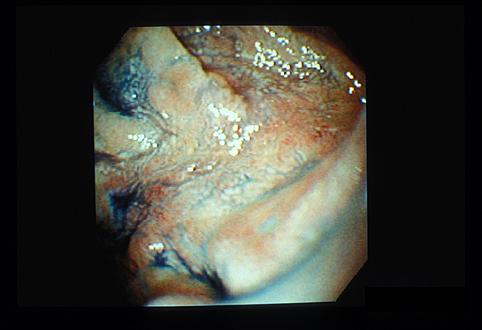

질환(병리주체)의 분류 악성 림프계종양/악성 림프종

부위(장기별) 십이지장/구부

검사방법 내시경

종양의 육안분류 0형(표재형)/IIc형(IIc)

종양의 최대경(밀리미터) 15~19